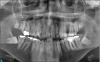

During the pre-examination interview, the patient complained about pain and said he was aware of cavities. He knew his mouth needed attention, but he noted financial concerns. Although he wanted to fix any potential condition, his main concern was maintaining a nice smile. Panoramic x-rays showed some challenges in this case due to the limitations set forth by the patient (Figure 1). He had multiple unsalvageable teeth, generalized periodontal disease, one stainless-steel crown and fillings that were failing, rampant initial and recurrent decay, and impacted third molars.